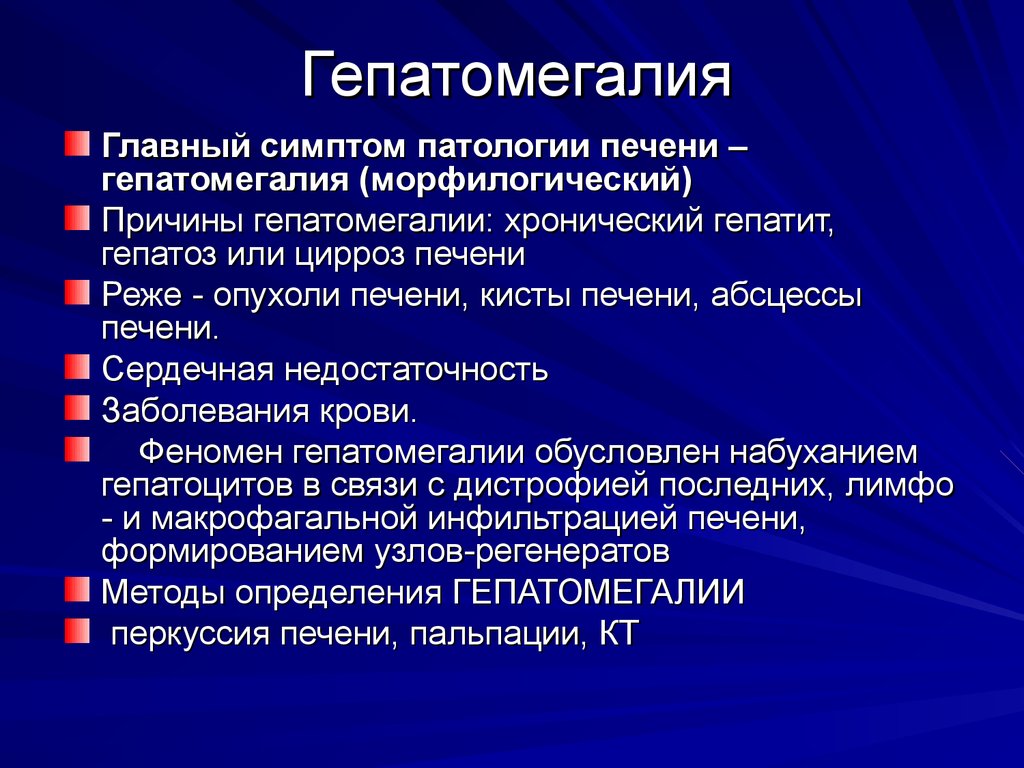

Очаговые симптомы опухоли затылочной доли. Клинические проявления опухоли лобной доли:. Опухоль мозга височной доли симптомы. Опухоль затылочной доли головного мозга. Гепатомегалия. Симптомы гепатомегалии. Умеренное увеличение печени. Умеренная гепатомегалия.

Гепатомегалия. Симптомы гепатомегалии. Умеренное увеличение печени. Умеренная гепатомегалия. Маммография косая проекция укладка. Маммография молочных желез. Маммография это исследование. Рентгеновская маммография.